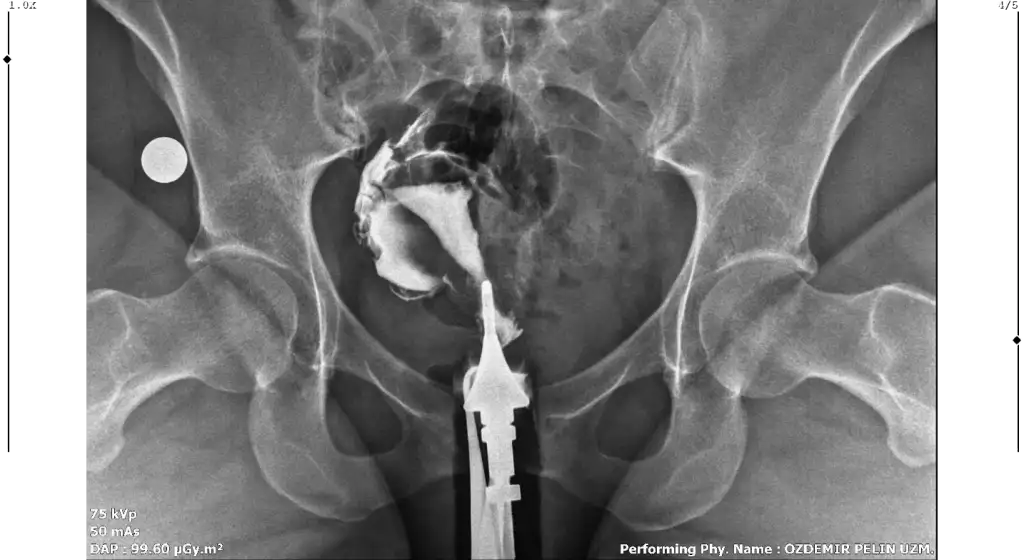

Merhaba, sağlıklı rahim gorseli ile kiyaslaninca sanki üstten biraz basık ama endişelenmeyin benim direk Y di belki çekim açısından olabilir, sizde sadece tüpleri anlayamadim dağılmış sanki açık tikaniklikda yok gibiMerhaba benim rahim filmim bu şekilde bir rapor oluşturulmadı filmi bugün çekildim doktora da gosteremedim. Yorumlanabilir misiniz?

Çok teşekkür ederim cevabınız içinMerhaba, sağlıklı rahim gorseli ile kiyaslaninca sanki üstten biraz basık ama endişelenmeyin benim direk Y di belki çekim açısından olabilir, sizde sadece tüpleri anlayamadim dağılmış sanki açık tikaniklikda yok gibi

Sizin yorumunuzu görünce bende hidrospenks baktım da sanki sağ tarafta boğum var gibi ama tek tüple de gebelik oluşuyor zaten benimde tıkalı malesef, yinede endişelenmeyin sakın korkuyorumda yorum yaparken yanlış anlaşılırim üzerim diyeGenişleme olabileceği söylendi yani sıvı olabilir dendi. Hidrosalpenks oluyor o var gibi geldi sanki bana

Anlayışınız için çok teşekkür ederim. Bakalım doktora gösterince net sonucu öğrenirim. Çok teşekkür ederim tekrardan.Sizin yorumunuzu görünce bende hidrospenks baktım da sanki sağ tarafta boğum var gibi ama tek tüple de gebelik oluşuyor zaten benimde tıkalı malesef, yinede endişelenmeyin sakın korkuyorumda yorum yaparken yanlış anlaşılırim üzerim diye

Ben de geçen hafta çektirdim HSG filmi. Raporum bugün oluştu ama anladığım kadarıyla sağ tüp açık sol tüp kapalı sanırım. Bana da yorumlama konusunda yardımcı olabilir misiniz? 4 senelik evliyim ve bebek sahibi olamadık, gebelik de hiç oluşmadı. Pcos'tan mustaribim. Tavsiyelerinizi alabilirim.

Merhaba bana da hidroselpenks gibi geldi çok hafif boğum var doktorunuzun yorumu ne oldu acabaMerhaba benim rahim filmim bu şekilde bir rapor oluşturulmadı filmi bugün çekildim doktora da gosteremedim. Yorumlanabilir misiniz?

Canım rahim yapısı güzelmişT tubiikk Ekledim görüntüleri, teşekkür ederim.

Sağ tüpün açık sol tüpün kapalıymış ben öyle anladım görüntüde de biri kapalı gözüküyor zaten

Doktor'un adı neydi hacettepe deki. Önerir misinizMerhabalar dün doktora gittim. ve 1 buçuk sene önce çekilen hsg görüntülerine bakıp doktor sen de perde olabilir ultrasonla bakalım dedi ve ultrasonda da gördü hatta bana da gösterdi rahim 2 ye ayrılıyor göz şeklinde ve histeroskopi ile ameliyat edicez sonra da tüp bebek dedi. ama ben zaten ocak ayında histeroskopi yaptırdım polip temizlendi.

doktor hacettepe de profesör. histereskopiyi özel hastanede yapacak 3500 tl dedi. kafam karıştı iyice 4 senedir düzenli olarak doktora gidiyorum. nasıl olur da diğer doktor göremez. benzer durum yaşayanlar var mı? başka doktora da gitmeli miyim? Lütfen Yardım!!!